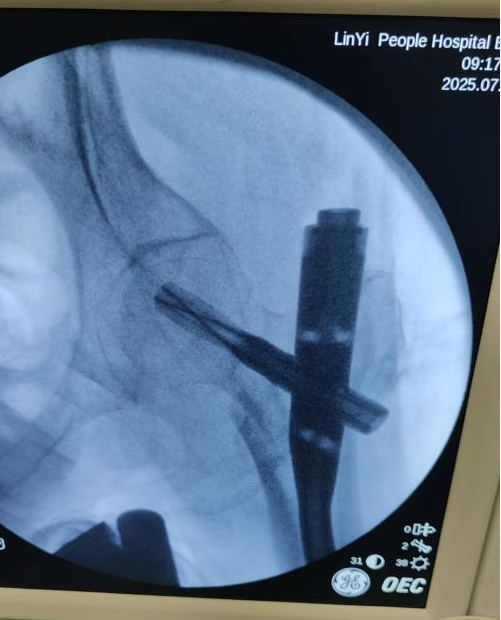

近日,临沂市人民医院创伤中心一病区通过多学科协作(MDT),先后为一位92岁和一位101岁的超高龄患者成功实施“闭合复位股骨近端髓内钉(PFNA)微创手术”,标志着我院超高龄骨折患者的救治水平迈上新台阶。

两例骨折患者均属于超高龄老人,且合并高血压、冠心病、肺功能不全及贫血等症状,属于理论上的手术禁区。但是主刀医生于晓东团队根据患者既往病史及入院病情评估,仍然认为手术是病人康复的最佳选择。在与患者家属充分沟通、征得家属同意后,手术团队迅速组织输血科、麻醉科、心内科、重症医学科的专家进行多学科会诊,制定了个性化手术方案:包括术前输血提高手术耐受,采用“超声引导下神经阻滞+轻剂量椎管内麻醉”避免全麻对心肺功能的抑制,使用PFNA微创髓内钉系统通过3个不足3cm的小切口完成固定,实施术后快速康复(24小时内启动抗凝、营养支持及早期康复训练)等措施。在精准缜密的手术方案支撑下,经相关科室密切配合,手术团队在最短时间内顺利完成手术,术后患者康复良好,得到患者及家属一致好评。

该两例手术的主刀医生于晓东教授介绍,“对于股骨粗隆间骨折的老年患者,只要患者身体条件允许,手术是首选方案。而且,微创技术可将手术时间控制在1小时内,出血量少于200ml,手术风险也大幅降低。科室近几年收治的80岁以上股骨粗隆间骨折患者中微创手术率达100%,1年生存率提升至85%。”